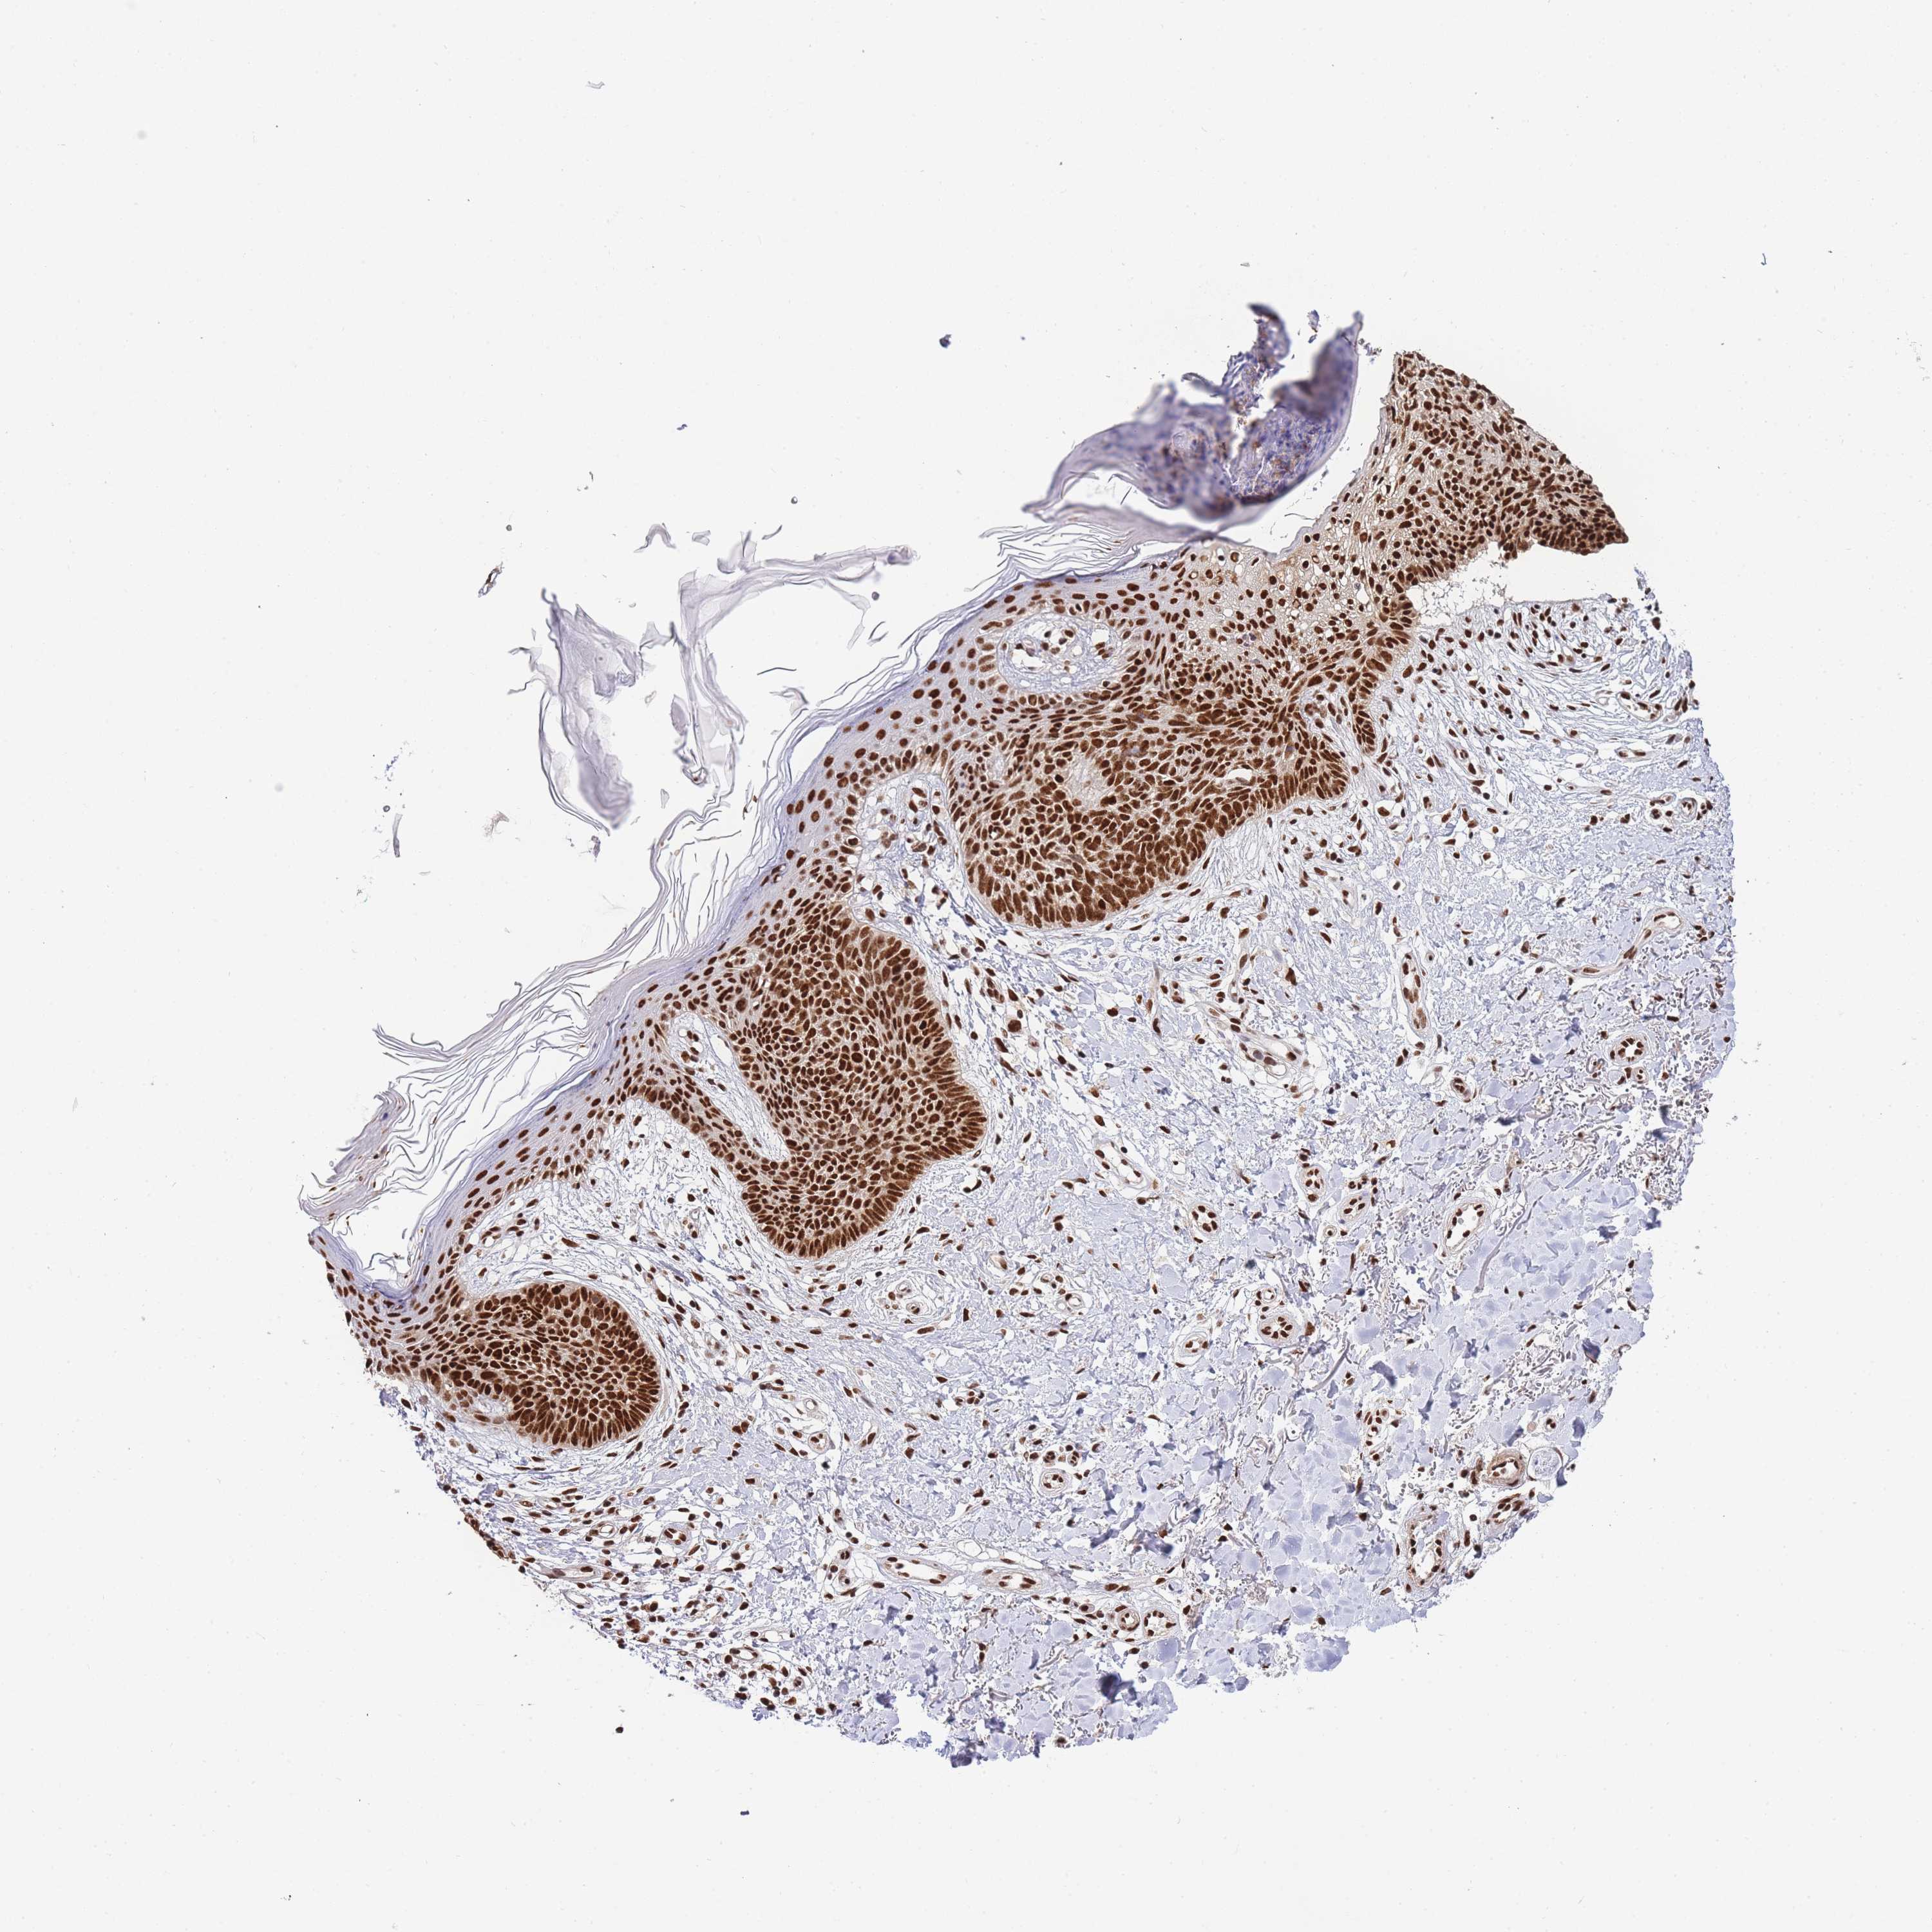

Basal cell and squamous cell cancer

SKIN CANCER - Protein expressioni

A mouse-over function shows sample information and annotation data. Click on an image to view it in a full screen mode. Samples can be filtered based on level of antibody staining by selecting one or several of the following categories: high, medium, low and not detected. The assay and annotation is described here.

Antibody stainingi

Antibody staining in the annotated cell types in the current human tissue is reported as not detected, low, medium, or high, based on conventional immunohistochemistry profiling in selected tissues. This score is based on the combination of the staining intensity and fraction of stained cells.

Each image is clickable and will lead to virtual microscopy that enables deeper exploration of all samples and also displays staining intensity scores, fraction scores and subcellular localization as well as patient and tissue information for each sample.

Antibody HPA035174

Antibody CAB005167

Staining

High

Medium

Low

Not detected

Intensity

Strong

Moderate

Weak

Negative

Quantity

>75%

75%-25%

<25%

None

Location

Nuclear

Cytoplasmic/membranous

Cytoplasmic/membranous,nuclear

Basal cell carcinoma